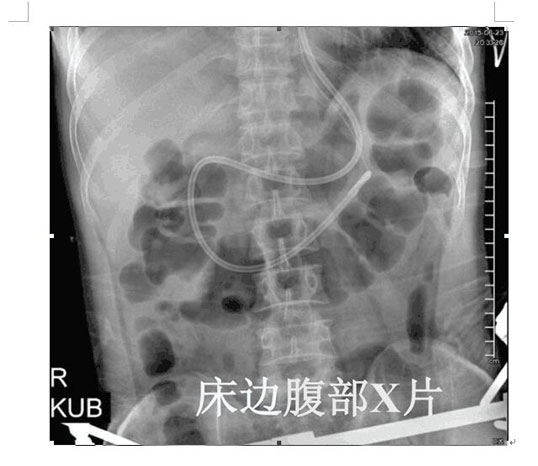

2017年4月22日,ICU成功開展了第一例床旁盲插經(jīng)鼻空腸管置入術(shù)并獲得成功。截止目前已為三位患者完成該術(shù),均為一次性盲插置管成功,臨床反映良好。此項技術(shù)的成功應(yīng)用,填補(bǔ)了我院在該護(hù)理技術(shù)領(lǐng)域的一項空白,標(biāo)志著ICU的護(hù)理技術(shù)水平邁上了一個新的臺階。

以往選擇在X線下或者使用胃鏡協(xié)助置入鼻空腸管,患者痛苦大且受輻射影響。而床旁徒手盲插經(jīng)鼻空腸管植入術(shù)是臨床護(hù)士在不依賴于其他輔助設(shè)備的情況下,通過一定的置管技巧,將管道插至十二指腸或空腸。此法省時、費用低、操作方便、損傷小,尤其對胃蠕動功能差的患者,不易引起食物反流、誤吸。鼻空腸管不僅可以從管內(nèi)注入營養(yǎng)液,而且還可以進(jìn)行胃腸減壓,值得臨床推廣。